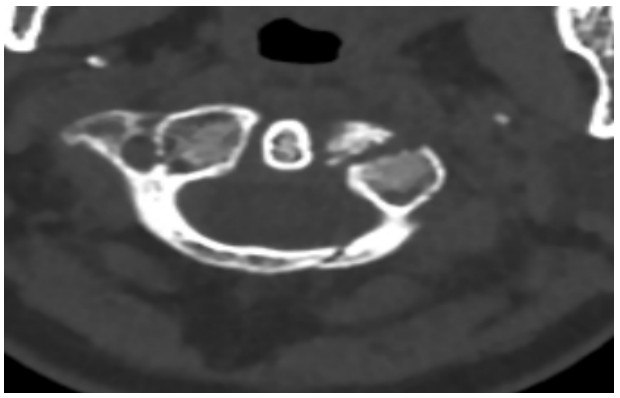

國慶節(jié)前一天,譚女士不幸被門框砸傷頸部,劇烈的疼痛和頸椎的活動受限讓她的世界瞬間陷入了黑暗。在經(jīng)歷了初步的檢查后,譚女士被診斷為寰椎骨折,這個診斷如同一道晴天霹靂,讓她和家人的心沉入了谷底。絕望中,譚女士被緊急轉(zhuǎn)至衡陽市中心醫(yī)院骨科一區(qū)(脊柱外科),錢軍博士及其團隊在接到這一緊急病例后迅速接診,經(jīng)過細致的病史詢問、體格檢查和影像學(xué)資料分析,確診譚女士的寰椎骨折伴有寰樞椎體不穩(wěn)定,迫切需要手術(shù)治療以恢復(fù)其穩(wěn)定性??紤]到上頸椎手術(shù)的高風(fēng)險性,特別是寰樞椎周圍結(jié)構(gòu)復(fù)雜,緊鄰椎動脈和脊髓,手術(shù)過程中的任何微小失誤都可能導(dǎo)致災(zāi)難性后果,錢軍博士團隊頂著壓力,迎難而上,沒有絲毫猶豫,立即行急診手術(shù),投入到緊張的救治工作中。